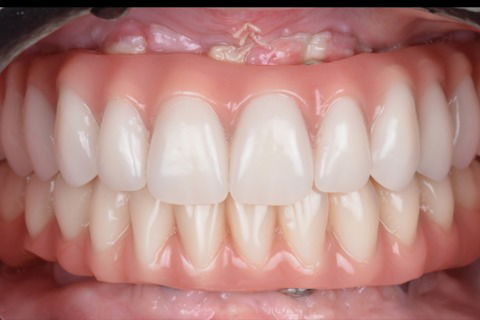

Sorriso final

Foto 17 Sorriso final